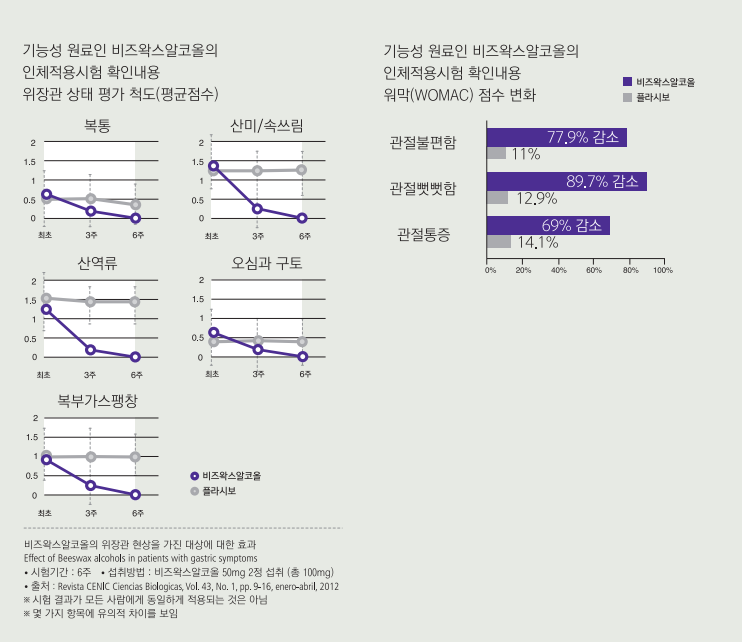

6주간의 비즈왁스알코올 인체적용시험 결과, 복통·속쓰림·위산 역류·오심·구토·복부가스팽창 등의 위장관 증상이 70%이상 개선을 확인했으며, 관절통증·관절뻣뻣함·관절의 물리적 기능 개선 효과도 확인되었다. 특히, 비즈왁스알코올은 관절염으로 소염진통제를 복용하고 위장관 증상을 겪고 있는 사람들에게 새로운 대안이 되고 있다.

비즈왁스알코올이 관절염으로 인한 진통제 복용율을 낮출 수 있다는 낮출 수 있다는 연구결과가 있다. 관절염을 앓고 있는 120명의 쿠바인을 대상으로 비즈왁스알코올 섭취 기간 동안 진통제 복용횟수를 비교했다. 비즈왁스알코올을 섭취하지 않은 사람들은 56.7%에서 진통제를 복용한 반면, 비즈왁스알코올을 섭취한 사람들의 진통제 복용율은 10%에 그쳤다.

이 연구를 포함, 여섯 편의 비즈왁스알코올 관련 논문을 분석한 결과에서 연구팀은 비즈왁스알코올은 환자들의 진통제 복용량을 크게 감소시켰으며, 이는 비스테로이드성 소염진통제(NSAID)를 복용하고 있는 관절염 환자들에게 매우 훌륭한 대안이 될 것이라고 밝히고 있다.

그 이유는 NSAID계의 약물들과는 달리 비즈왁스알코올은 위십이지장에 손상을 입히지 않으면서 염증을 줄이고 위점막을 보호하는 2가지 역할을 동시에 하기 때문이라고 설명하고 있다.